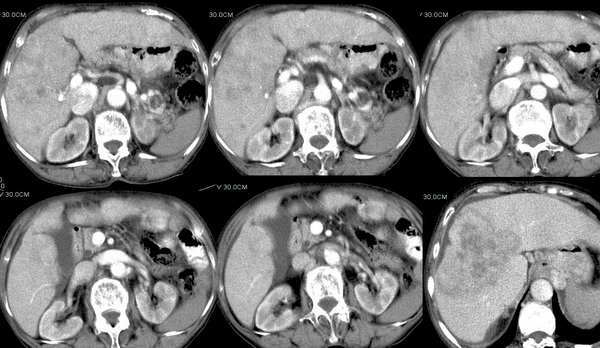

女性,77岁,上腹部不适,下肢浮肿,无其它不良.

今年三月份ct平扫检查.

今天复查ct平扫

动脉期

门脉期

延时期10分钟及12分钟

可以肯定为肝癌;首先要指出的是,这个病例的三期扫描不规范,动脉期时间太早了,而门脉期的表现却是动脉期的表现,肾脏皮髓质交界清晰,说明处在动脉期但又略晚了点,看肝癌表现,以动脉晚期最为可靠,即动脉显影明显,脾脏呈花斑样强化,门脉初步显影,此表现为诊断肝癌最可靠的时期。这个病例肝脏有硬化表现,合并腹水,增强后病灶明显强化且边界不清,肝动脉异常增粗,门脉右支受侵,右后叶也有一处小病灶,为子灶。我的诊断为:肝右叶原发浸润型肝癌,肝硬化,门脉高压,腹水。下肢浮肿,可能为下腔静脉癌栓形成。